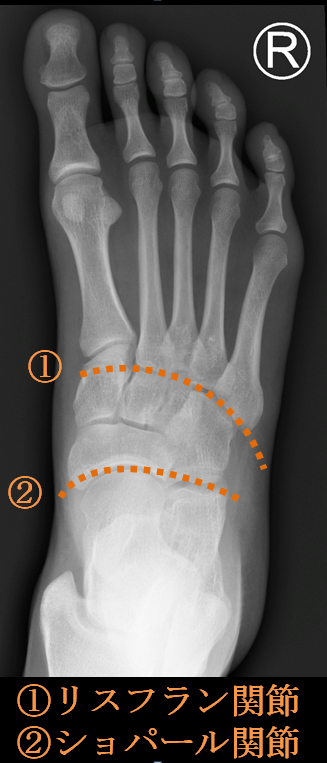

椎体、顔面、頭部の単純撮影法 | 診療放射線技師国家試験 対策ノート。椎体、顔面、頭部の単純撮影法 | 診療放射線技師国家試験 対策ノート。椎体、顔面、頭部の単純撮影法 | 診療放射線技師国家試験 対策ノート。折れや擦れはあります。。足部側面撮影 (立位荷重撮影), Foot lateral view (weight。気になる方はご遠慮ください。歯科矯正メカニクス -その普遍性と臨床応用- Ⅱ